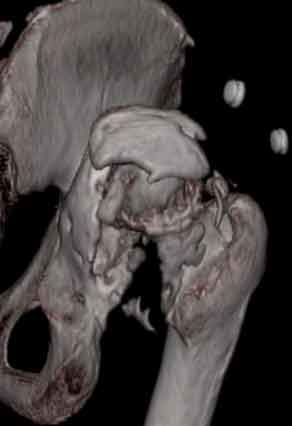

Уважаемые коллеги, пациент 30 лет, 4 года назад попал под поезд, ампутация обеих голеней в в/3, подвздошный вывих бедра (теперь застарелый). несмотря на такую ситуацию, пациент вполне прилично ходит и объем движений в неоартрозе близок к неповрежденной стороне. Основная жалоба - боль при нагрузке и в покое. Планируем двухэтапное лечение: резекция шейки, мобилизация проксимального отдела бедра, низведение бедра АВФ, вторым этапом б/ц эндопротезирование. Как поступить с головкой, вроде бы при протезировании можно будет обойтись без пластики, или ошибаюсь? Оставить ее там, где она есть? Другие варианты лечения.